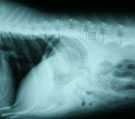

レントゲンにて胃内に円形の異物確認 内視鏡にてペットボトルのキャップ確認 摘出したペットボトルのキャップ

経過:一般状態良好。腹部レントゲンにて胃内にペットボトルのキャップと思われる円形の異物を確認した。胃の大きさに比べてかなり大きく吐き出させるのは困難と判断した。24時間絶食後、全身麻酔下にて胃内視鏡検査を施行した。ただちに白いペットボトルのキャップを確認できたが、通常の把持鉗子でも、バスケット鉗子でも、摘出不能であった。最も大きな把持鉗子を用いてやっと噴門を通過できたが、食道に滞留してしまった。外科用の長い鉗子を経口的に挿入して内視鏡観察下に直接把持して咽喉頭部分を通過させた。処置時間は4時間19分もかかってしまった。翌日、無事退院。